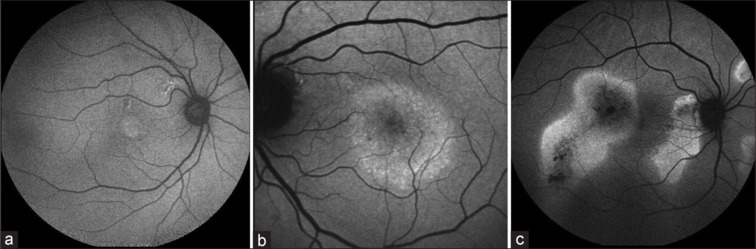

目的:本研究的目的是评估慢性中心性浆液性脉络膜视网膜病变(cCSC)患者的光学相干断层扫描(OCT)和吲吲胺绿血管造影(ICGA)生物标志物作为阈下纳秒激光(NSL)治疗反应的潜在指标。方法:回顾性分析32例NSL术后cCSC患者的36只眼。高缓解(HR)定义为首次NSL治疗后3个月视网膜下液(SRF)完全消退,完全缓解(FR)定义为最后一次NSL治疗后3个月SRF完全消退,所有NSL发作均发生在首次NSL后1年内。生物标志物包括中央黄斑厚度(CMT)、中央凹下脉络膜厚度(SFCT)和漩涡间静脉吻合(IVA)。结果:患者平均年龄54±12岁;86%为男性。基线OCT显示平均CMT为364±130µm, SFCT为292±45µm;ICGA中IVA占64%。HR为50%,FR为78%。较高的IVA率(83%对44%,P = 0.03)预示首次NSL后的不良反应。与没有IVA存在的患者相比,基线时有IVA存在的患者需要一次以上NSL治疗的可能性具有统计学意义(57%对15%,P = 0.02)。结论:OCT和ICGA生物标志物可作为NSL解剖反应的指标。IVA患者在基线时表现出较差的第一反应,可能需要重复激光治疗。

Purpose: The aim of the study was to evaluate optical coherence tomography (OCT) and indocyanine green angiography (ICGA) biomarkers in patients with chronic central serous chorioretinopathy (cCSC) as potential indicators of response to treatment with subthreshold nanosecond laser (NSL).

Methods: In this retrospective study, we examined 36 eyes of 32 cCSC patients after NSL. High response (HR) was defined as complete resolution of subretinal fluid (SRF) 3 months after first NSL treatment, full response (FR) as complete resolution of SRF, 3 months after the last NSL, with all NSL sessions occurring within 1 year from the first NSL. Biomarkers included central macular thickness (CMT), subfoveal choroidal thickness (SFCT), and intervortex venous anastomosis (IVA).

Results: Patients were 54 ± 12 years old on average; 86% were male. OCT at baseline showed a mean CMT of 364 ± 130 µm and SFCT of 292 ± 45 µm; 64% showed IVA in ICGA. HR was seen in 50% and FR in 78%. Higher IVA rates (83% vs. 44%, P = 0.03) predicted poor response after the first NSL. Patients with IVA presence at baseline showed a statistically significant higher likelihood of requiring more than one NSL session compared to those without IVA presence (57% vs. 15%, P = 0.02).

Conclusion: OCT and ICGA biomarkers may play a role as indicators of anatomical responses to NSL. Patients with IVA at baseline showed a poor first response and may need repetitive laser treatments.